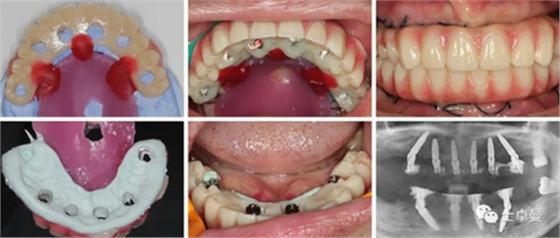

制作牙支持固位釘導板,固位釘支持種植導板,以及固位釘輔助就位的臨時修復體;

以期利用牙支持式導板的高精確性完成全程引導下的種植手術(shù)。

外科手術(shù)過程

上頜種植手術(shù)

常規(guī)消毒碧藍麻局麻下,利用牙支持式導板確定固位釘位置后取下導板;

然后分離牙齦,于牙槽嵴頰腭側(cè)略翻瓣暴露牙根與牙槽骨間隙,切除齦瓣邊緣炎性肉芽組織,拔除上頜16-27牙,球鉆清理拔牙窩,并用大量生理鹽水沖洗;

通過先前固位釘位置安放固位釘支持式種植導板,因拔牙前后軟硬組織變化較大,需耐心尋找先前固位釘位置;

導板就位后利用Straumann BLT全程導板工具盒全程備洞,取下導板后利用測量桿確認種植體窩方向和深度以及種植窩周圍骨量;

植入6顆Straumann BLT種植體,植入扭矩均達到45Ncm以上:

16、26:4.1mm×14mm

14、24:4.1mm×12mm

12、22:3.3mm×12mm

安裝SRA基臺,均加力至35Ncm:

16、26:RC30°4mmA型

14,24:RC17°2.5mmA型

12,22:NC17°2.5mmA型

旋入SRA基臺保護帽,修整粘膜,縫合。

a10.png

下頜種植手術(shù)

手術(shù)操作流程與上頜基本一致,最終植入4顆Straumann BLT種植體,植入扭矩均達到45Ncm以上:

35、45:4.1mm×14mm

32、42:3.3mm×12mm

35、45:RC30°4mmA型

32、42:NC直型2.5mm

a11.png

a12.png

手術(shù)完成后復查CBCT與術(shù)前設(shè)計對比,驗證植入精度。